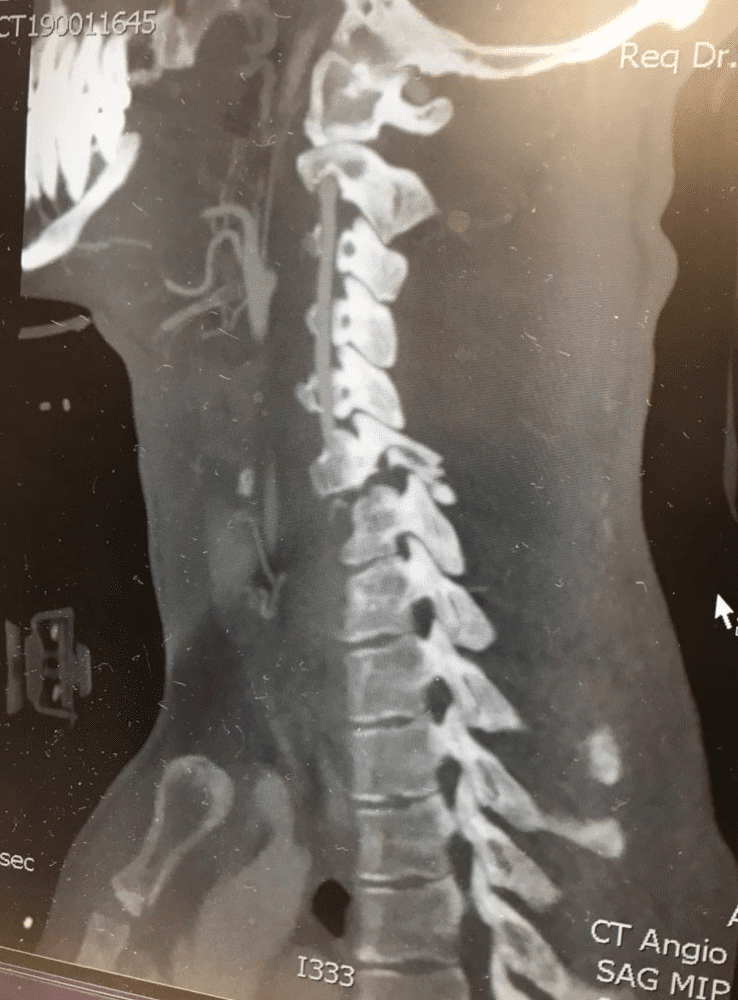

Earlier this month on January 14, 2019, Blake Savage crashed while riding at a private supercross track in Mesquite, Nevada, sustaining a cervical spinal cord injury due to fractures to his C6 and C7 vertebra. Savage was immediately transported to Dixie Regional Medical Center in St. George, Utah, where his injuries were assessed and a surgical plan was quickly put into place. On Tuesday, January 15, Savage underwent successful surgery, where doctors completed a C5 to T1 posterior spinal instrumentation and fusion, which addressed the fractures and stabilized the spine.